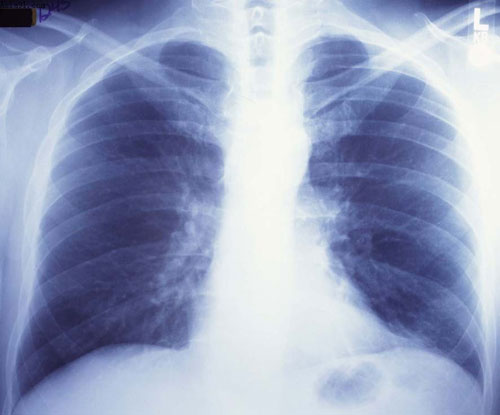

照片名称:正常胸片